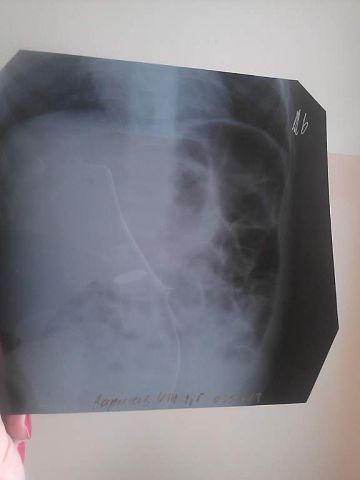

вот страх -то меня охватил. Позвонили в скорую, время то ко сну приближается, Сказали ехайте сюда, как раз рентгенолога везут, мы рванули, сделали рентген, обнаружили пропажу в желудке.